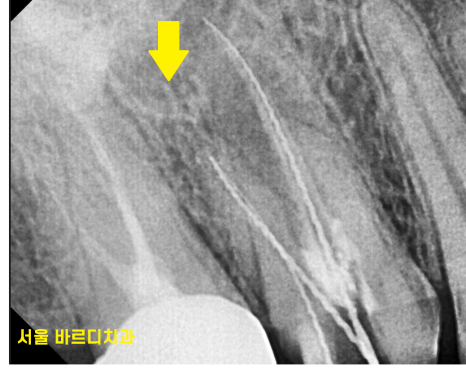

예전에 신경치료를 할 때

신경을 제거 후 치료를 마무리 하면서

하얀 재료로 세균이 침투되지 않게 밀봉을 해놓는데요.

이 재료를 제거

x-ray를 봐서는

염증이 없어진건지 잘 모르시겠죠~?

변화가 된 모습만 비교해드릴께요~

뿌리 절반 이상 염증들이

3달의 치료과정을 통해

손톱만큼 줄어들었습니다.